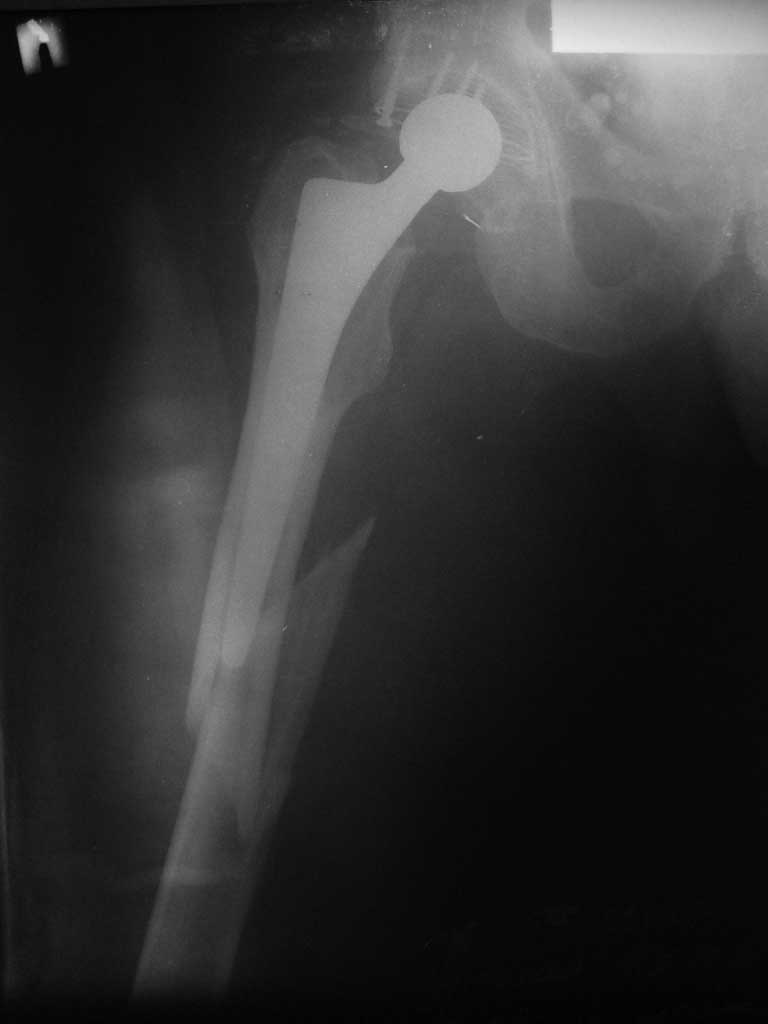

[Ortho] Перипротезный перелом

Имя     : ppfcompressed.jpg